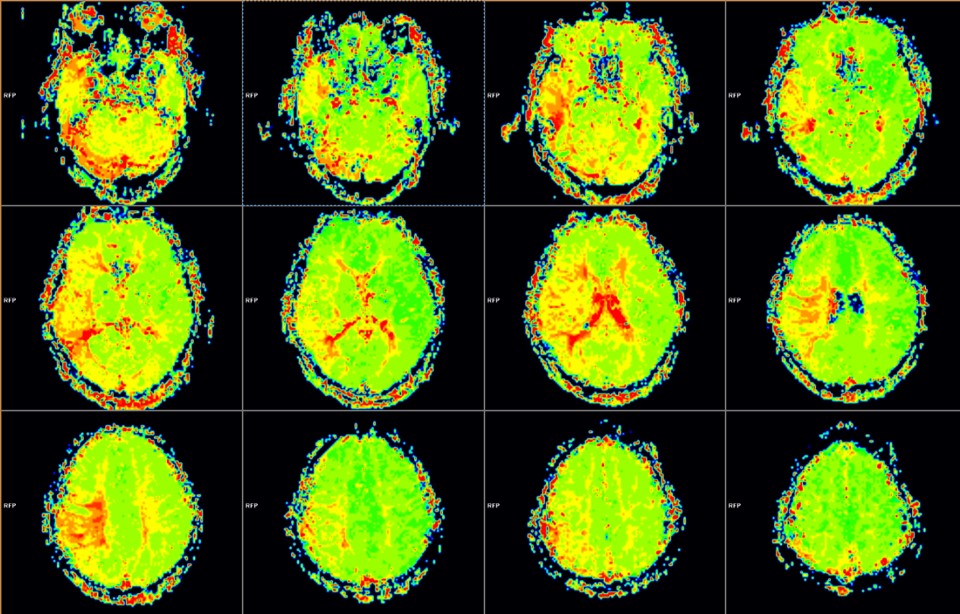

术后1周MRI PWI显示:右侧颞叶、半卵圆区、顶下小叶MTT较术前改善。

PWI显示:右侧颞叶、额叶下部、半卵圆区、顶叶PTT延长范围较术前缩小。